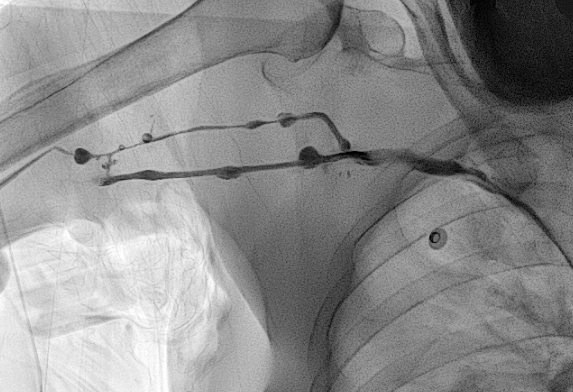

1. PICC 삽입 얼마나 걸려요?

PICC 삽입에는 그리 긴 시간이 소요되지 않습니다.

시술 자체는 3분 내지 5분이 걸립니다.

소독이 끝나고 시술자가 들어오고 나서는 대략 3분에서 5분 걸린다고 보시면 됩니다.

2. PICC 삽입이 오래 걸리는 경우

b. 혈관이 막혔거나 아주 좁은 경우

오랜 기간 동안 PICC 를 가지고 계셨거나, 독한 약물 치료를 받으신 분들 중에는 말초 정맥이 막혀버렸거나 아주 좁아져버린 분들이 계십니다. 이 경우 찔렀던 혈관을 그대로 이용하려면 풍선 카테터를 이용하여 혈관성형술을 하거나, 아니면 다른 혈관을 새로 찔러 들어가야 합니다. 두 해결 방법 모두 시간을 늘어지게 하는 방법이지요.